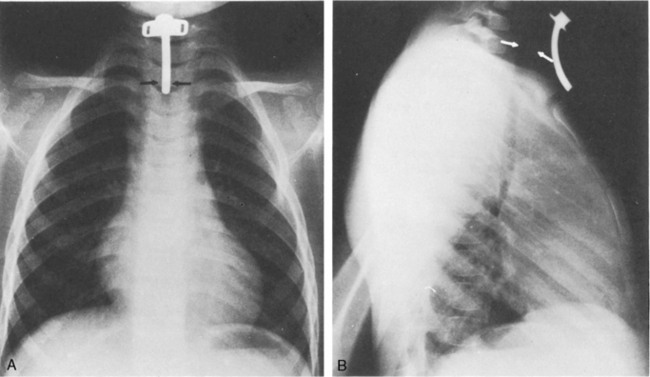

The aortic knob and the trachea will be displaced if a mediastinal shift occurs. When significant atelectasis is present, the trachea and aortic knob usually are displaced toward the area of collapse, because of the volume loss associated with the atelectais.22 However, if a large pleural effusion or pneumothorax is present, the trachea and aortic knob typically will be displaced away from the involved lung and toward the unaffected side, because these problems represent volume gain in the chest (Fig. 10-10).

image

Fig. 10-10 Tension pneumothorax. This 5   month old with complex congenital heart disease was noted by the nurse to have respiratory distress, including tachypnea and nasal flaring. The nurse also noted decreased breath sounds and chest expansion in the left chest and tracheal deviation to the right. This supine anteroposterior film was obtained and demonstrated a left-sided tension pneumothorax (white arrows). The trachea (black arrow) and aortic knob are displaced away from the involved left hemithorax and toward the unaffected right side because of the increased volume associated with the pneumothorax.